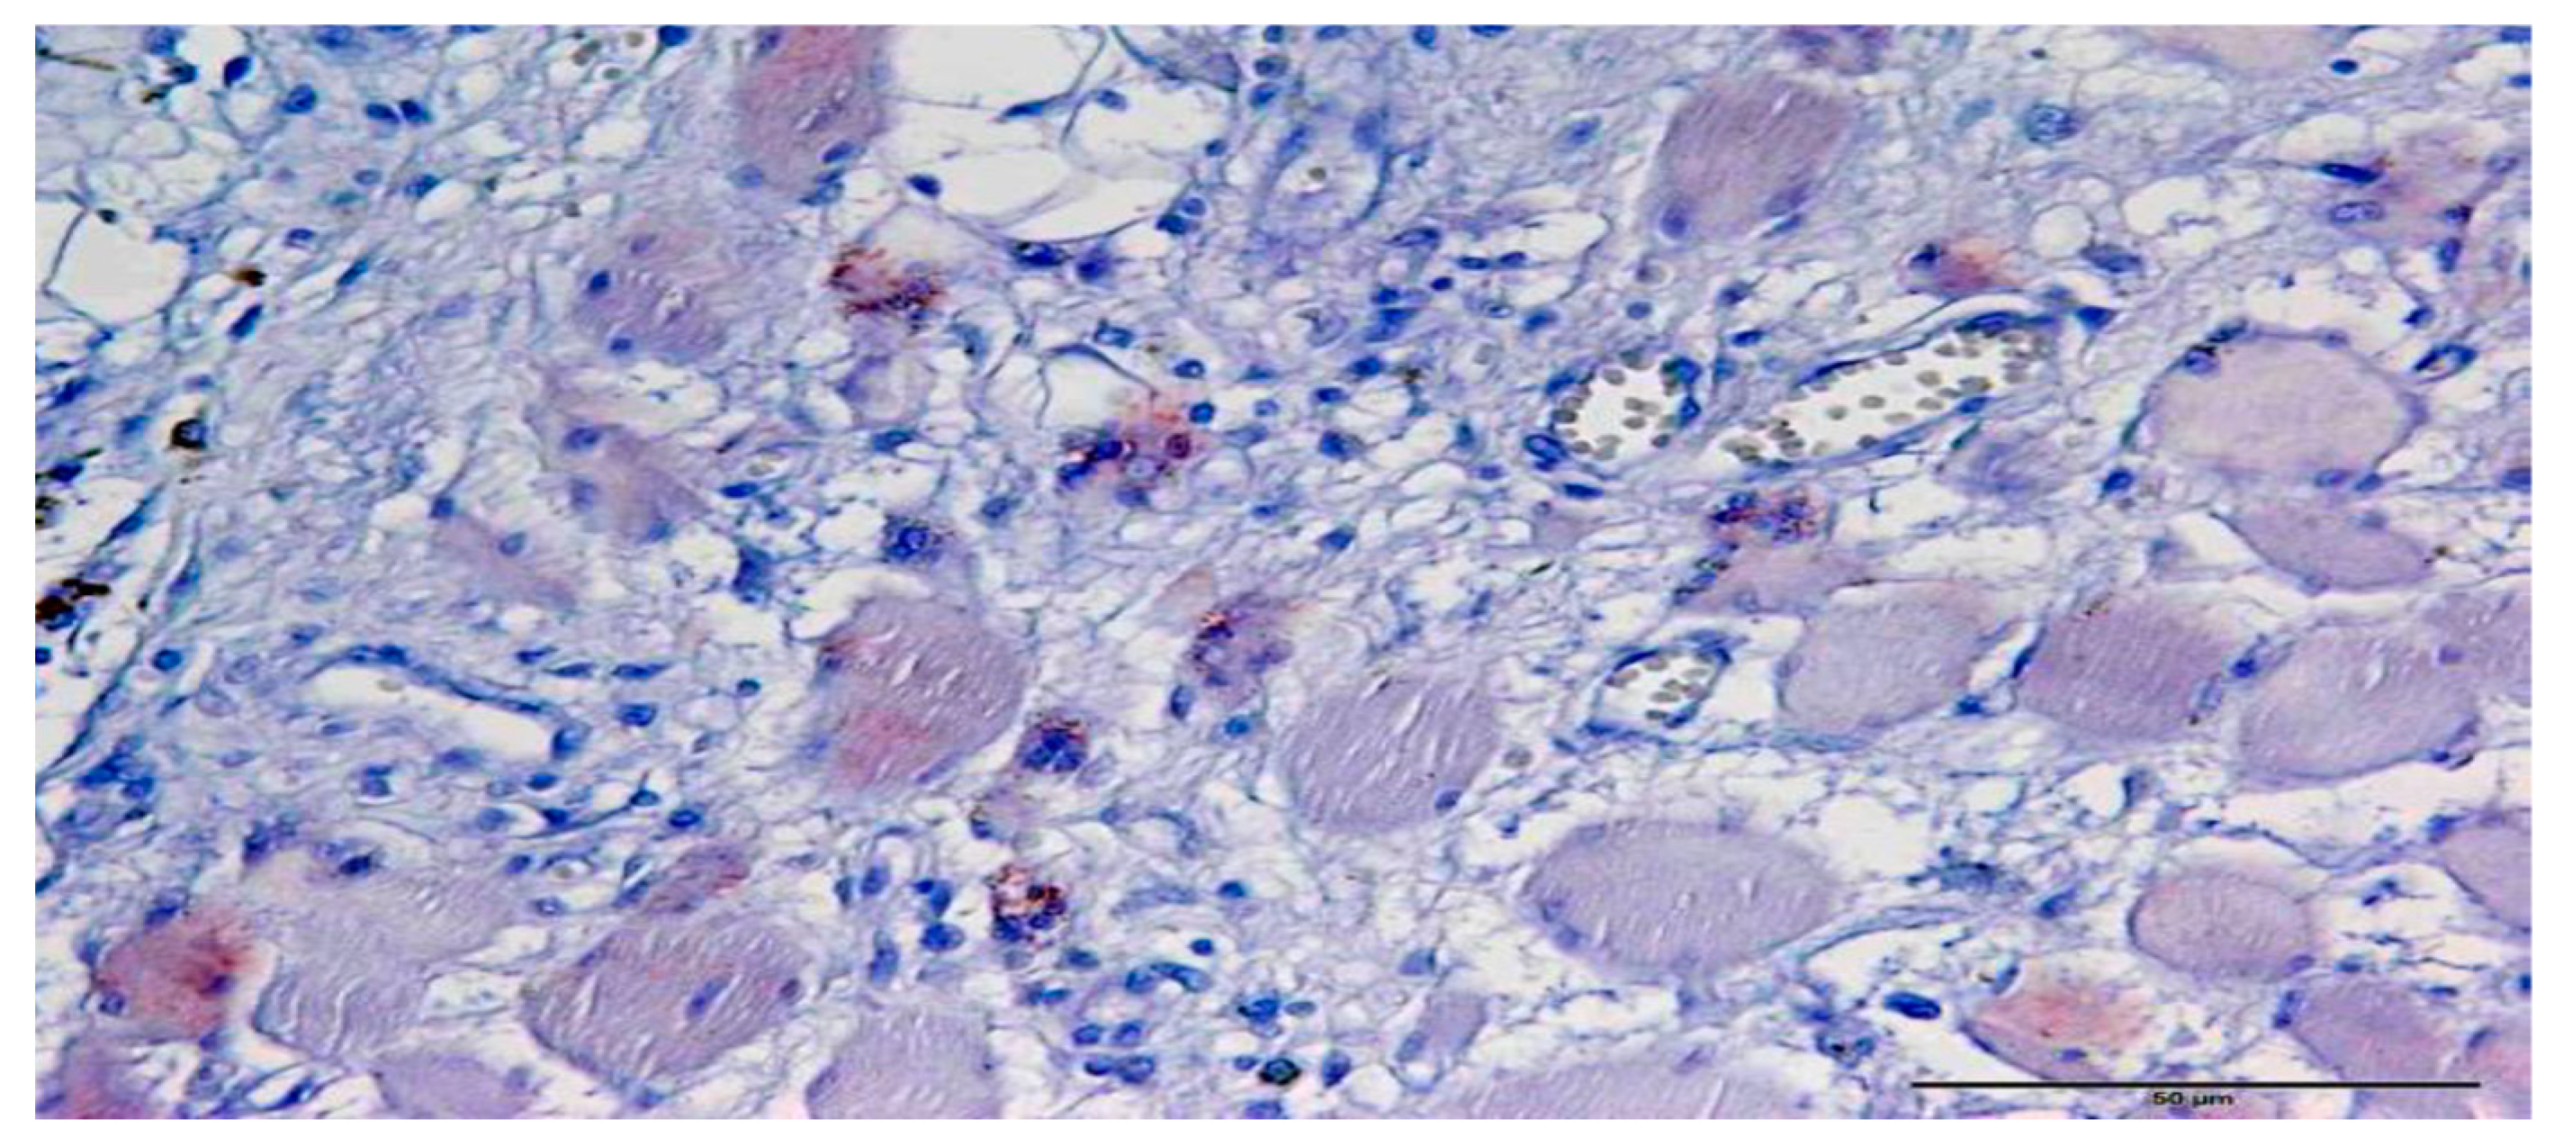

2.2. Immunohistochemistry

2.3. Immunohistochemical Scoring for Shh and Gli1

3.1. Immunohistochemistry